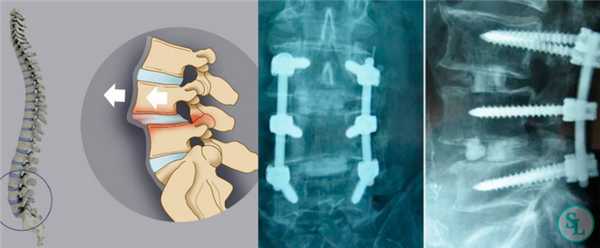

Спондилодезом называют хирургическое вмешательство, являющееся разновидностью артродеза. Целью операции является обездвиживание одного или нескольких позвоночно-двигательных сегментов. Это достигается за счет установки специальных конструкций, которые надежно фиксируют между собой подлежащие сращению позвонки. В результате они со временем они прочно срастаются, что полностью исключает возможность движения и развития на фоне этого болезненных ощущений.

Чаще всего пациентам проводится удаление межпозвоночных грыж и установка на место резецированных межпозвонковых дисков специальных кейджей. Только такой комплексный подход обеспечивает полное устранение болевого синдрома и надежную профилактику их возникновения в связи с поражением этого же позвонково-двигательного сегмента в будущем.

При заднем типе хирург получает возможность проводить манипуляции на позвоночнике, рассекая кожу, фасции и раздвигая в стороны глубокие мышцы спины. Это позволяет меньше травмировать ткани, поэтому реже приводит к возникновению нежелательных последствий и обеспечивает более легкое и быстрое протекание реабилитационного периода. Проведение спондилодеза через задний доступ в подавляющем большинстве случаев стало возможным благодаря созданию титановых кейджей, в составе которых присутствует костная крошка. Это специальные имплантаты, устанавливаемые вместо удаленных межпозвонковых дисков. Они пришли на смену костным или искусственным имплантатам и значительно повысили безопасность и эффективность хирургического вмешательства.

Но особенно результативным, по данным проведенных исследований, является межтеловой спондилодез. Поскольку тела позвонков значительно лучше снабжаются кровью, имеют большее количество клеточных элементов и отличаются высоким потенциалом к образованию новой костной ткани, имплантированные между ними объекты приживаются значительно лучше, чем установленные между отростками позвонков. При таком способе фиксации успешного спондилодеза удается добиться в 96% случаев. В противном случае позвонки могут не срастись, что приведет к сохранению болей в спине, а в дальнейшем к тяжелым последствиям.

Метод PLIF подразумевает удаление отростков с двух сторон от позвонка. После этого осуществляется радикальная дискэктомия. По обеим сторонам позвонка устанавливаются кейджи.

Методика TLIF признана наименее травматичной. Она подразумевает удаление межпозвоночного диска и осуществление спондилодеза со стороны наиболее выраженного стеноза.